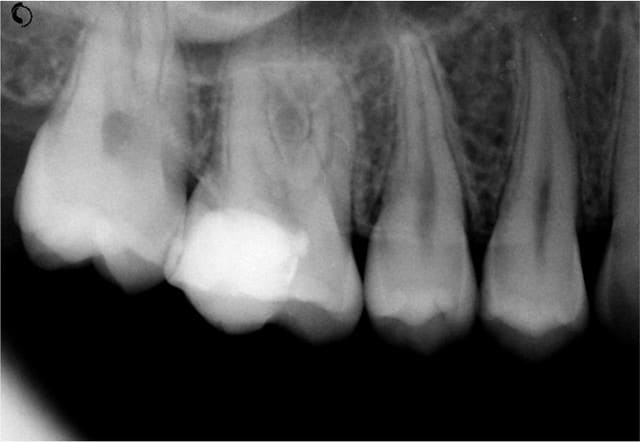

Par comparaison, quelques photos de coiffage pulpaire au CO²

entre la photo 7 et 9, quelle est l'étape effectuée? Je trouve les impacts tres marqués et noirs, comment sont-ils éliminés, il nya aps d'échauffement de surface?

Après hémostase, stérilisation et vitrification, la carbonisation est facilement éliminée aux US et si besoin avec du Negatol (un antiseptique). Cette carbonisation peut être évitée et son importance dépend du matériau ou du tissu traité, elle peut aussi servir à la détection de dentine infiltrée. Les protéines sont déstructurées à 60°, l’effet thermique en mode superpulse ou chopérisé est bactéricide et la puissance crête peut atteindre 200W mais son absorption reste très limitée (0.1mm) donc sans danger pour la pulpe.